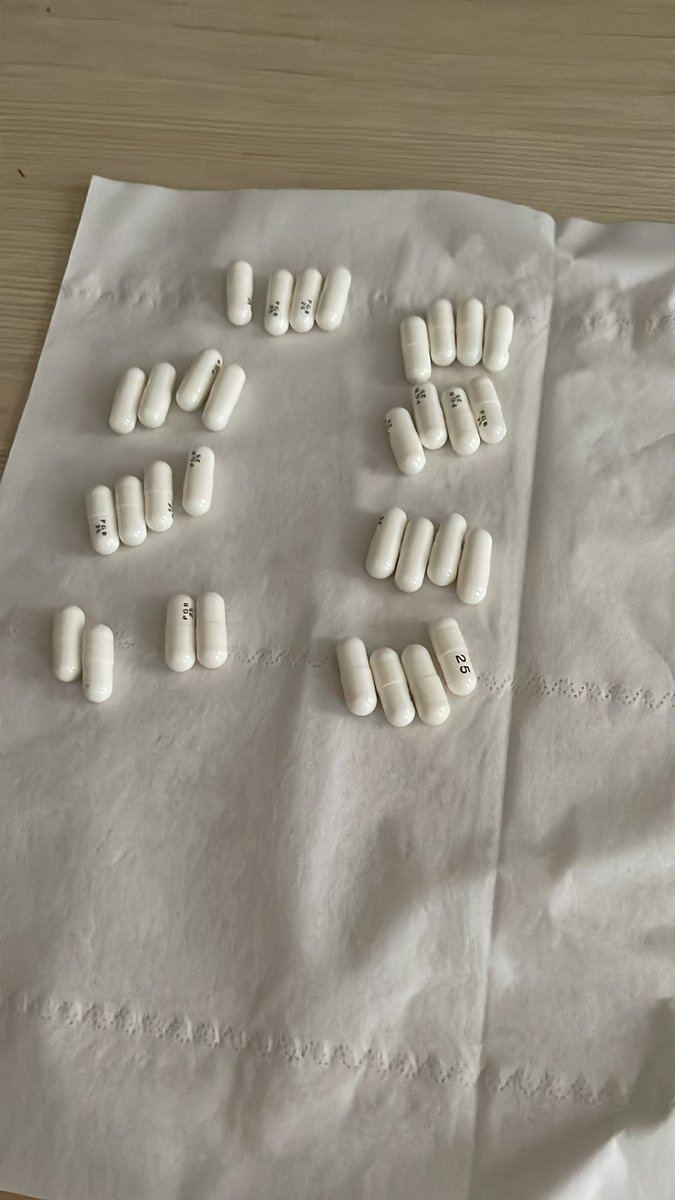

对于药物过量引起的中枢神经系统副作用,有一些不常见或常见的药物来控制症状。

评论区欢迎补充 https://t.co/7S4tGVDEM5